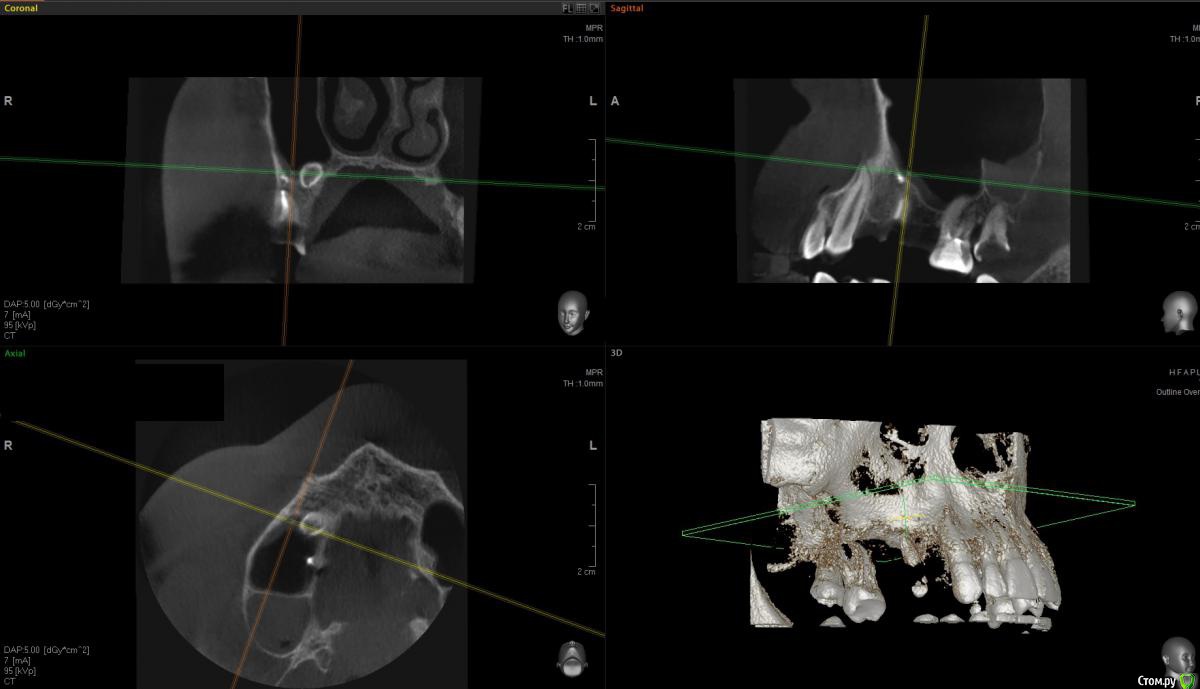

Пришел пациент с вопросом о 1.5. Поговорили о варианте одномоментного всего. Ушел на КТ. Принес такое.

Я сначала решил, что в пазухе новообразование. Посмотрев внимательнее подумал что корень. Оказалось нечто среднее - недоформировавшийся корень, вросший в стенки пазухи.

Ах да, забыл совсем. Удалил по ходу действия 1.8, обратите внимание на пазуху по КТ - септа в проекции 1.7 так удачно отделила отекшую слизистую от области синуса)